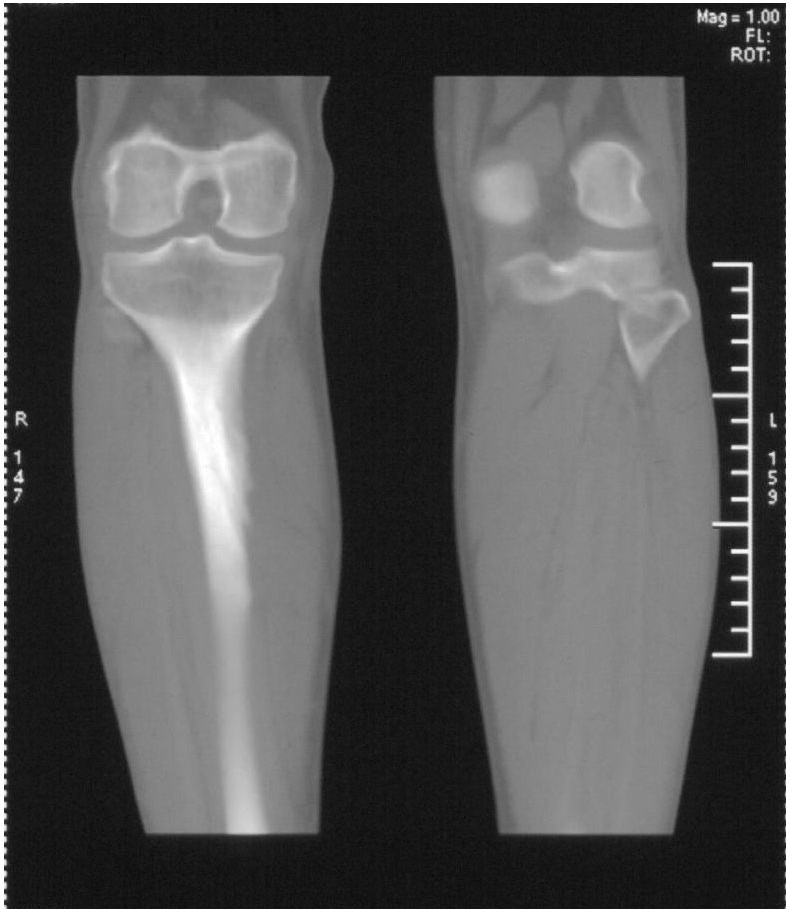

男,42岁。4个月前钢筋钝伤右侧小腿部,当时因无明显外伤,未引起重视。一周后因受伤腿部疼痛,发现肿胀,随后到当地医院进行检查(2008年4月16日)。因未发现骨质异常未引起重视,仅仅进行口服抗生素治疗处理。经过一段时间治疗但未见明显治疗效果在5月29日又进行x线检查,发现有胫骨密度上段密度增高,又进行抗炎治疗,仍未见效果。又在7月3日进行x线检查,仍然报告有胫骨上端密度增高,并建议ct检查。以下是相关检查结果:

髓腔密度呈絮状增高,胫骨上端内侧可见层状骨膜反应,考虑骨髓炎.

髓腔密度呈絮状增高,胫骨上端内侧可见层状骨膜反应,肌间隙模糊,考虑骨髓炎.

破坏、增生、骨膜反应,考虑骨髓炎